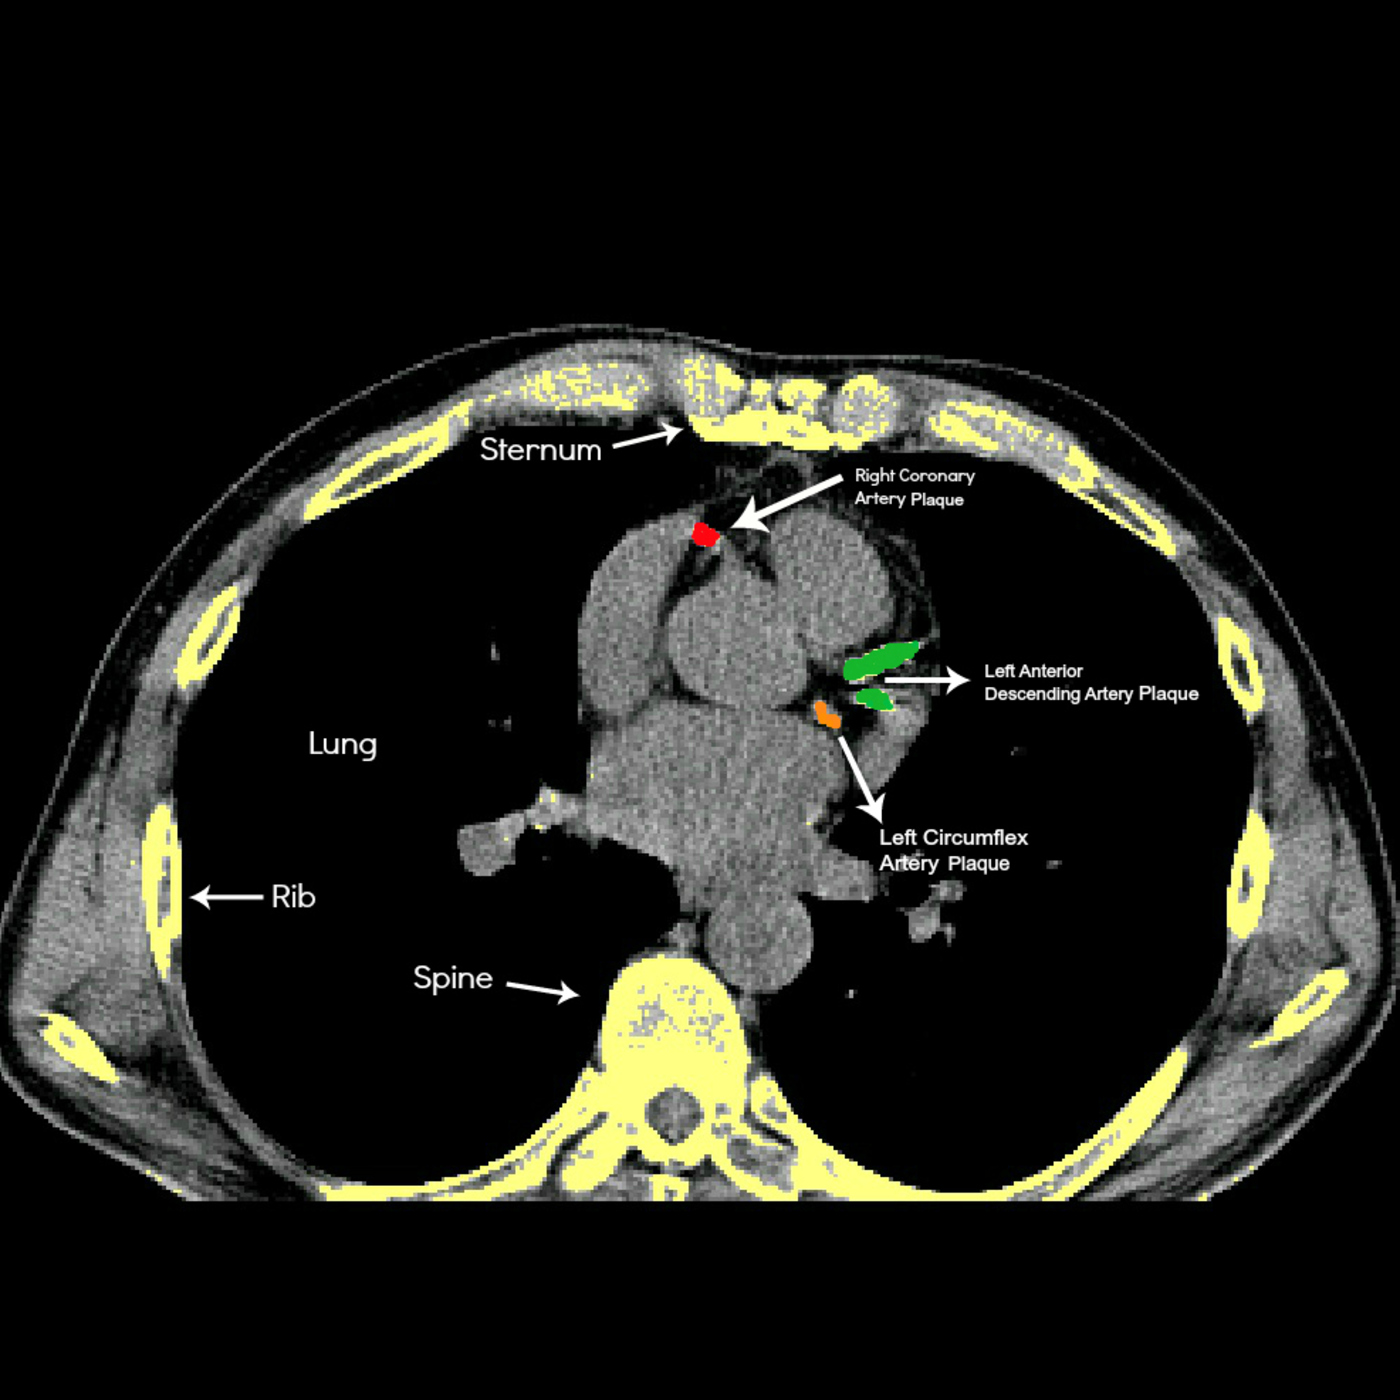

This is a quick 20 minute podcast covering everything you need to know about finding and reversing your heart disease. Find out the truth about blockages,stents,and angiograms. Find out what to do about a positive score.